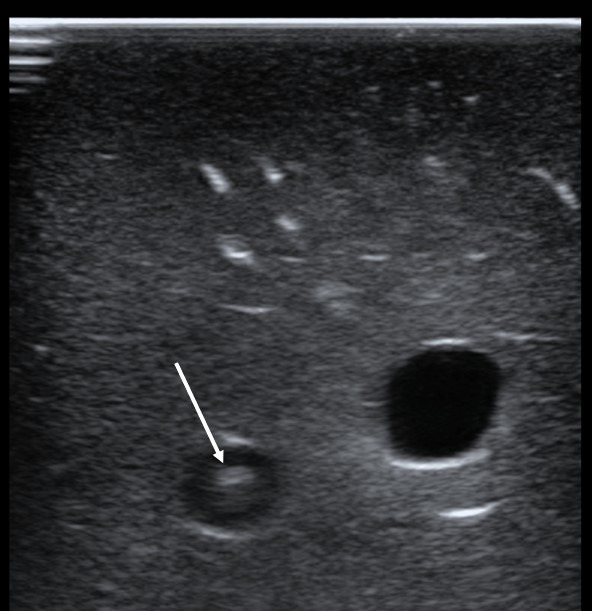

Background: Visualization of the guidewire during internal jugular (IJ) vein catheterization by point of care ultrasound (POCUS) has been recommended for avoiding inadvertent carotid artery dilation. The purpose of this study was to determine the accuracy of POCUS for identifying guidewires inappropriately placed in the carotid artery. Methods: This prospective, observational study involved emergency medicine (EM) residents with varying experience in guidewire visualization. Using an inanimate model, investigators placed guidewires randomly into the carotid artery or IJ vein. Residents, blinded to guidewire location, scanned the model and recorded their findings. The test performance of POCUS for arterially placed guidewires was evaluated through calculation of sensitivity, specificity, negative predictive value (NPV), positive predictive value (PPV), and overall accuracy, using investigator placement as the non-reference standard. Results: Twenty-five residents performed 51 observations. The test performance of POCUS for identifying arterially placed guidewires was sensitivity 95.0% (95%CI = 73.1-99.7%), specificity 96.8% (95%CI = 81.5-99.8%), NPV 96.8% (95%CI = 81.5-99.8%), and PPV 95.0% (95%CI = 73.1-99.7%). The overall accuracy was 96.1% (95%CI = 86.8-98.9%). Residents reported being very confident in their findings in 88.2% of all observations (95%CI = 76.6-94.5%), somewhat confident in 9.8% (95%CI = 4.3-21.0%), and not very confident in 2.0% (95%CI = 0.4-10.3%). No errors occurred among upper-level residents (post-graduate years 2-3) or those reporting >5 prior wire visualizations in live patients. Conclusions: This study is the first to demonstrate that physicians can easily identify misplaced guidewires located in the carotid artery with a high degree of accuracy using POCUS. We recommend routine scanning of the IJ vein and carotid artery prior to vessel dilation to reduce the likelihood of carotid artery injury.

Abstract Image